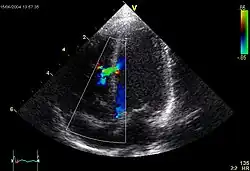

Die genauere Diagnostik wird (etwa nach einem in einer Vorsorgeuntersuchung beim Abhören festgestellten Herzgeräusch, hier einem lauten systolischen Geräusch über der Mitte des Brustbeins) heute mit Hilfe der Echokardiografie durchgeführt. Eine Herzkatheteruntersuchung bringt genauere Werte und wird durchgeführt, wenn die Echokardiographie keine ausreichenden Informationen für die Operation ergibt.